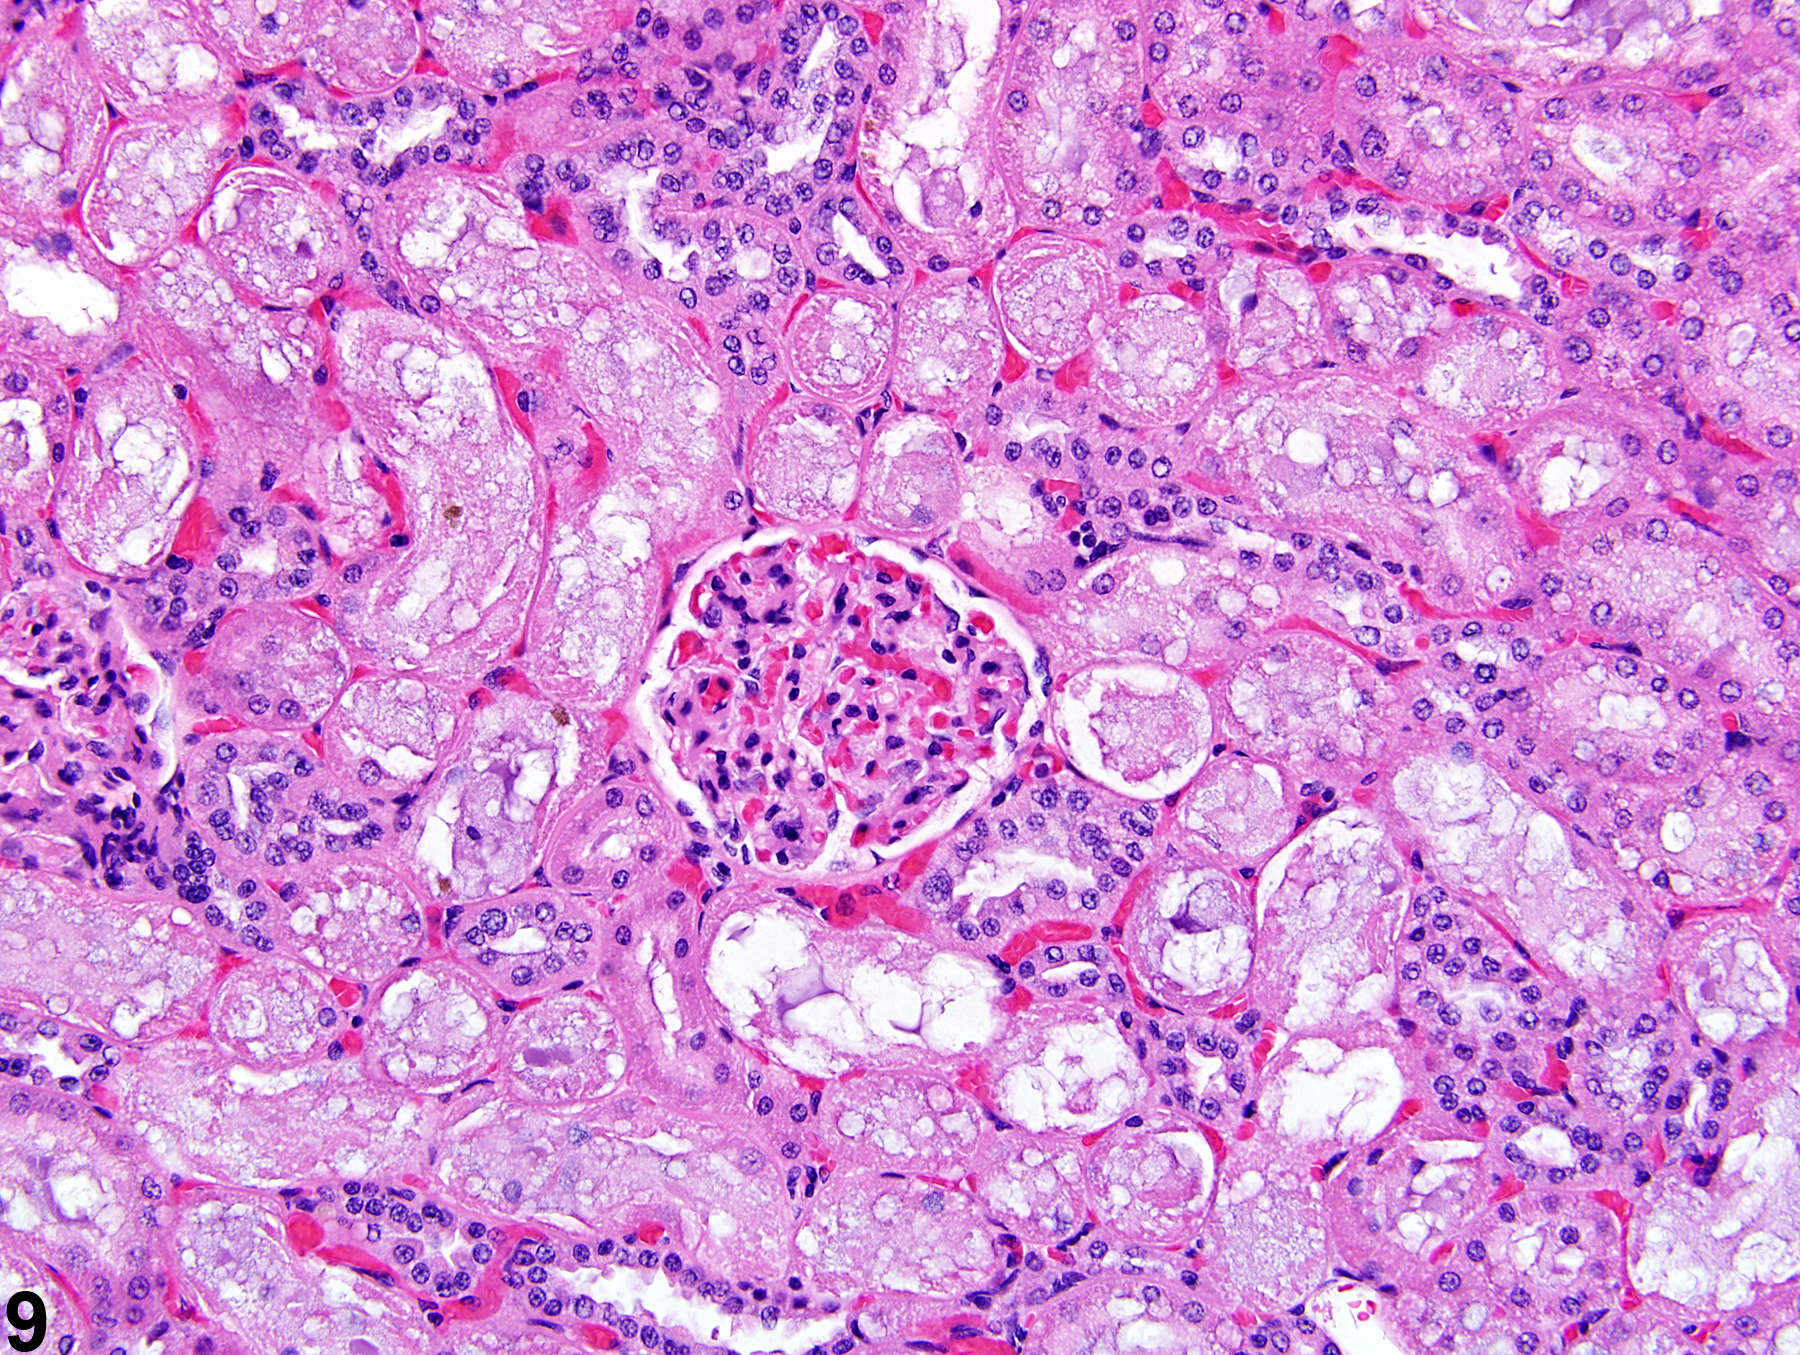

Межуточный миокардит: гистологические исследования